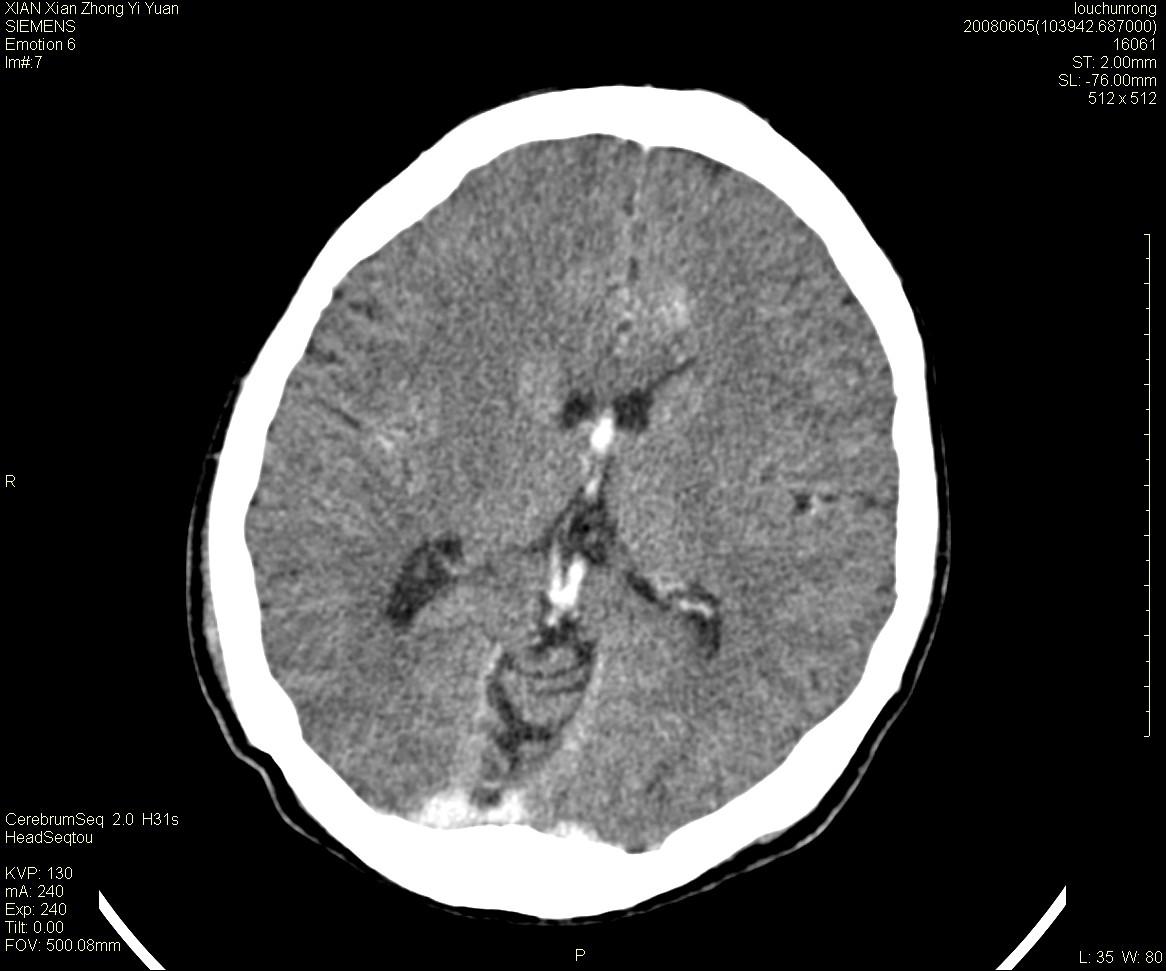

标题: CT13860:F52Y,,头外伤致头晕半天,以前无不适。 [打印本页]

标题: CT13860:F52Y,,头外伤致头晕半天,以前无不适。

层厚2mm。

左侧侧室内血管异常增粗,考虑血管变异或血管瘤可能,余未见异常

大家看左额叶大脑镰旁高密度影

两侧脑室体部距离增宽,胼胝体发育不良?

中线附近、枕叶近枕骨处及脑内多发点条状强化影,考虑血管异常?

大脑大静脉池内的密度不均,双侧脑室增宽,我看右异常这块。战友们看看

侧脑室前角变形、变窄,考虑侧脑室粘合;余未见明显异常。